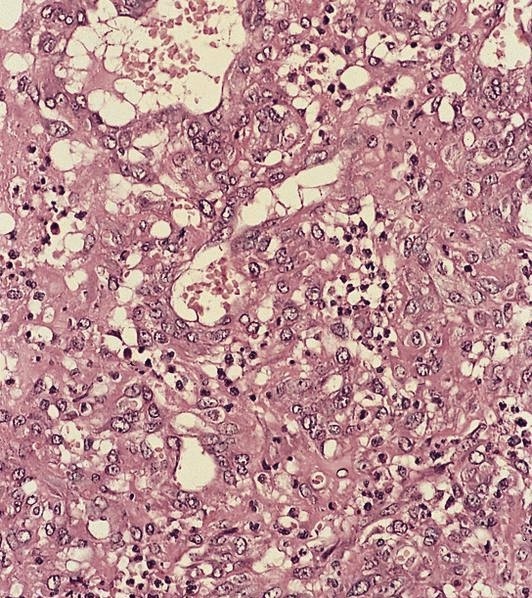

Microscopic (histologic) description

- Nodes show partial / complete effacement by storiform pattern of bland spindle cells, some with vacuoles

- Numerous vessels lined by plump endothelial cells, plasma cells and lymphocytes

Microscopic (histologic) images

Contributed by AFIP and Chunyu Cai, M.D., Ph.D. (Case #532)